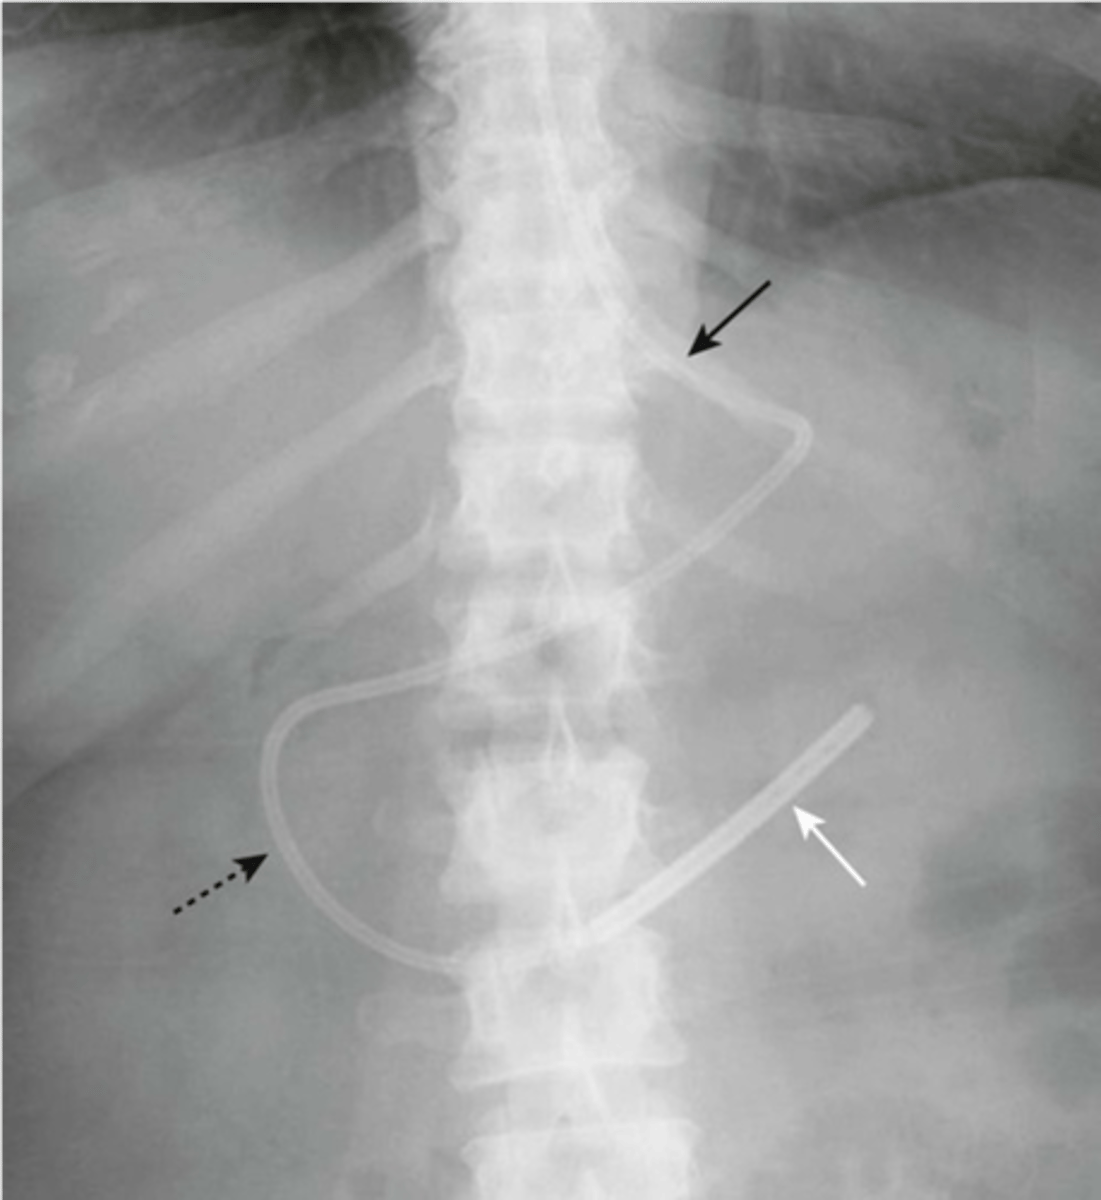

tube should extend about 10cm

Nasogastric tube (NGT)

-tip should be in 2nd or 3rd portion of duodenum

dobhoff tube (DHT)

-free air under diaphragm